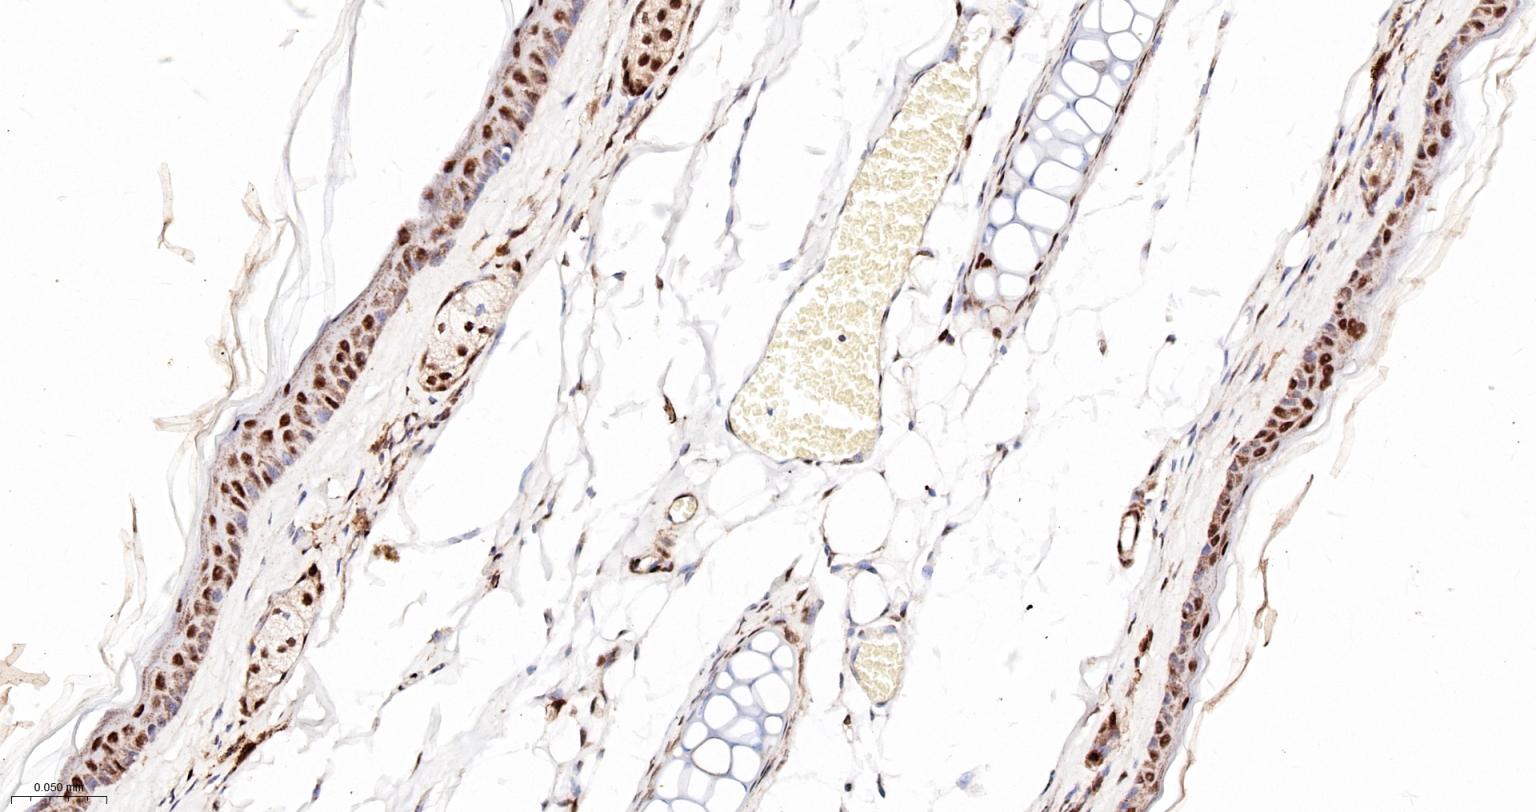

Paraformaldehyde-fixed, paraffin embedded Human Skin; Antigen retrieval by boiling in sodium citrate buffer (pH6.0) for 15 min; The section was incubated with PRPF19 Monoclonal Antibody, Unconjugated (bsm-61268R) at 1:200 overnight at 4°C, followed by conjugation to the bs-0295G-HRP and DAB (C-0010) staining.